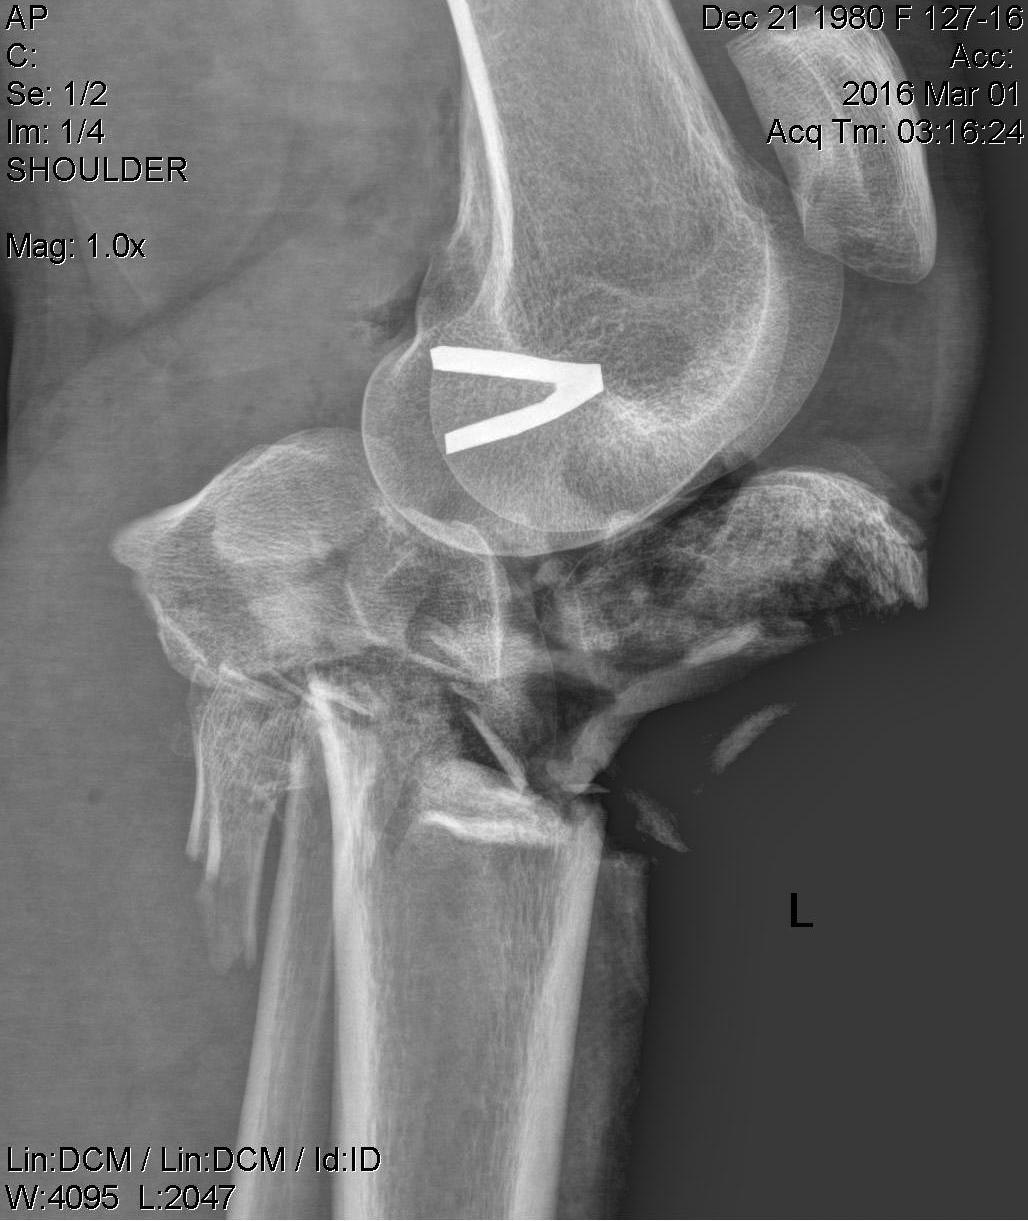

Имеется: Закрытый перелом диафиза левой локтевой кости. Закрытый оскольчатый перелом диафиза левой бедренной кости в средней трети. Открытые (3a-b) оскольчатые внутрисуставные переломы проксимального отдела обеих костей правой и левой голени. (см. снимки)

При поступлении выполнено: ПХО открытых перелом костей правой и левой голени, фиксация в аппаратах; фиксация перелома левой бедренной кости в аппарате; иммобилизация левого предплечья лонгетой.

Что делать с переломами костей левой голени пока не решили окончательно. Пока мнение коллег такое: оставить все как есть до заживления /консолидации и ортопедические проблемы с коленным суставом и укорочением (3-4 см) решать в отдаленном периоде – эндопротезирование (?).